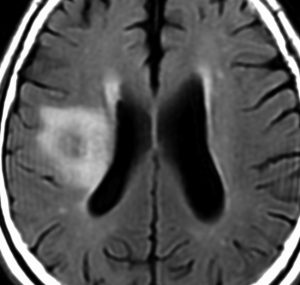

60代の患者さんの右前頭葉深部から島回に発生したものです。初発症状は症候性てんかんです。

ガドリニウム増強される腫瘍の中心部に壊死があり,悪性神経膠腫としては腫瘍周囲浮腫が強すぎるように見えるので,リンパ腫 PCNSLに似た画像所見です。